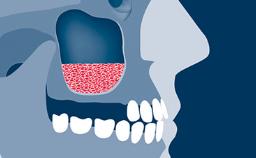

Radiography plays an important role in implant dentistry.

These investigations are used to assist in the diagnosis of pathology, aid in implant treatment planning, and monitor peri-implant bone levels on maintenance assessments, such as this image taken at a 1-year follow-up visit.

- describe errors and artifacts that can affect 2D imaging, and how to deal with them

- describe the errors and artifacts that can affect 3D imaging, and how to deal with them